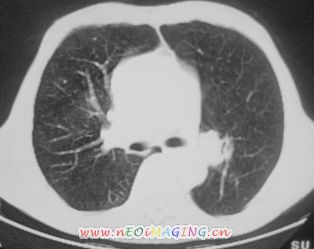

以下是引用南沙在2007-10-7 10:44:00的发言:[br]左下肺不张.[br]肺癌可能性大?

以下是引用卜一在2007-10-7 9:38:00的发言:[br]左下肺胸膜下团片影,内见含气支气管像,临近胸膜未见增厚。多考虑:1 左下肺炎症,建议消炎后复查!2 不除外肺隔离症合并感染!